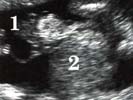

Echographiquement : -Absence permanente de visualisation de la vessie alors que

-Haut appareil urinaire normal

-Quantité de LA normale

-Muqueuse vésicale saillante au niveau de la région sous-ombilicale